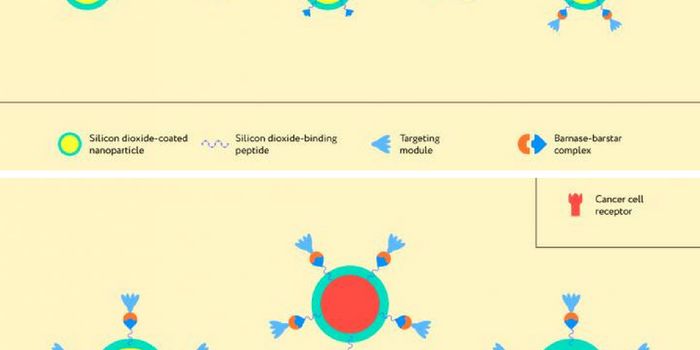

APR 25, 2018CancerResearchers are looking to biotechnology to enhance the detection of diseases including cancer. A group utilized the co ...

JAN 20, 2022Clinical & Molecular DXNanoparticles—tiny spheres carrying a biologically-active cargo—have the potential to transform how w ...